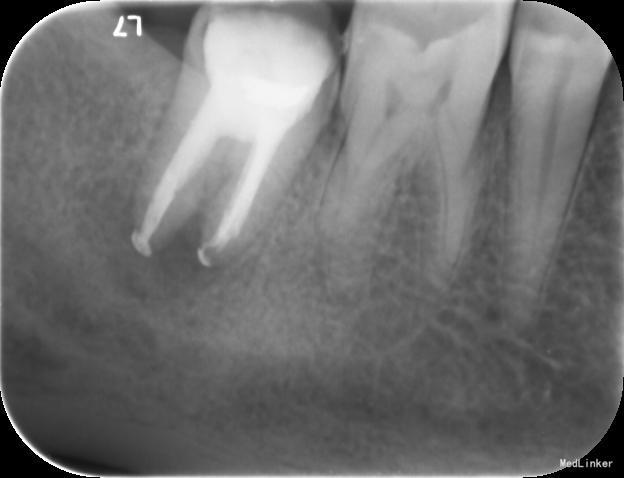

检查:右下7髓腔开放,可见髓腔内食物残渣及部分银汞充填体,叩痛(++), 冷热刺激无反应,松动1度,牙体已制备,牙合龈距离低,X线片示根尖区密度减低区。

诊断:难治性根尖周炎 治疗计划:告知患者病情,治疗难度及预后,拟行根管再治疗,但术后效果不确定,如若不理想拟需行根尖手术甚至牙拔除术。患者知情同意,并要求尽量行保留牙齿治疗。 处置:第一次 揭全髓顶,去腐,疏通根管,测量工作长度,机扩预备至S1,超声荡洗,激光消毒,封CP球。口服抗炎药。一周后复诊。 第二次 复诊无叩痛,暂封物在。去除暂封物,双氧水和盐水交替冲洗,EDTA伴随下根管预备至F2,超声荡洗,激光荡洗+激光消毒,封氢氧化钙。两周后复诊。 第三次 复诊无叩痛,暂封物在。 去除暂封物,双氧水和盐水交替冲洗,EDTA伴随下根管预备至40号,超声荡洗,激光荡洗+激光消毒,封vitapex,玻璃离子体充填。拍X线片。一月后复诊。 第四次 复诊无疼痛 旧充填体在 拍X线片可见根尖阴影变小,故未行任何治疗,嘱患者1月后再次复诊。 第五次 复诊无疼痛 旧充填体在 拍X线片未见根尖阴影变小,故去除旧充填体,冲洗,去除vitpex,根管再次预备,双氧水和盐水交替冲洗,超声荡洗,激光荡洗+激光消毒,封氢氧化钙。两周后复诊。 第六次 复诊无疼痛 去除暂封物,冲洗,见根管内无渗出,试尖,超声荡洗,激光荡洗和消毒,干燥,AHplus糊剂和热牙胶充填,糊剂超填,玻璃离子体充填。请口腔外科医生会诊是否可行根尖手术,外科医生建议因手术难度大,且病变与下颌神经管接近,建议随诊观察,暂不考虑行根尖手术。必要时考虑意向性牙再植术或者牙拔除术。嘱患者1月后复诊,结果患者失诊。